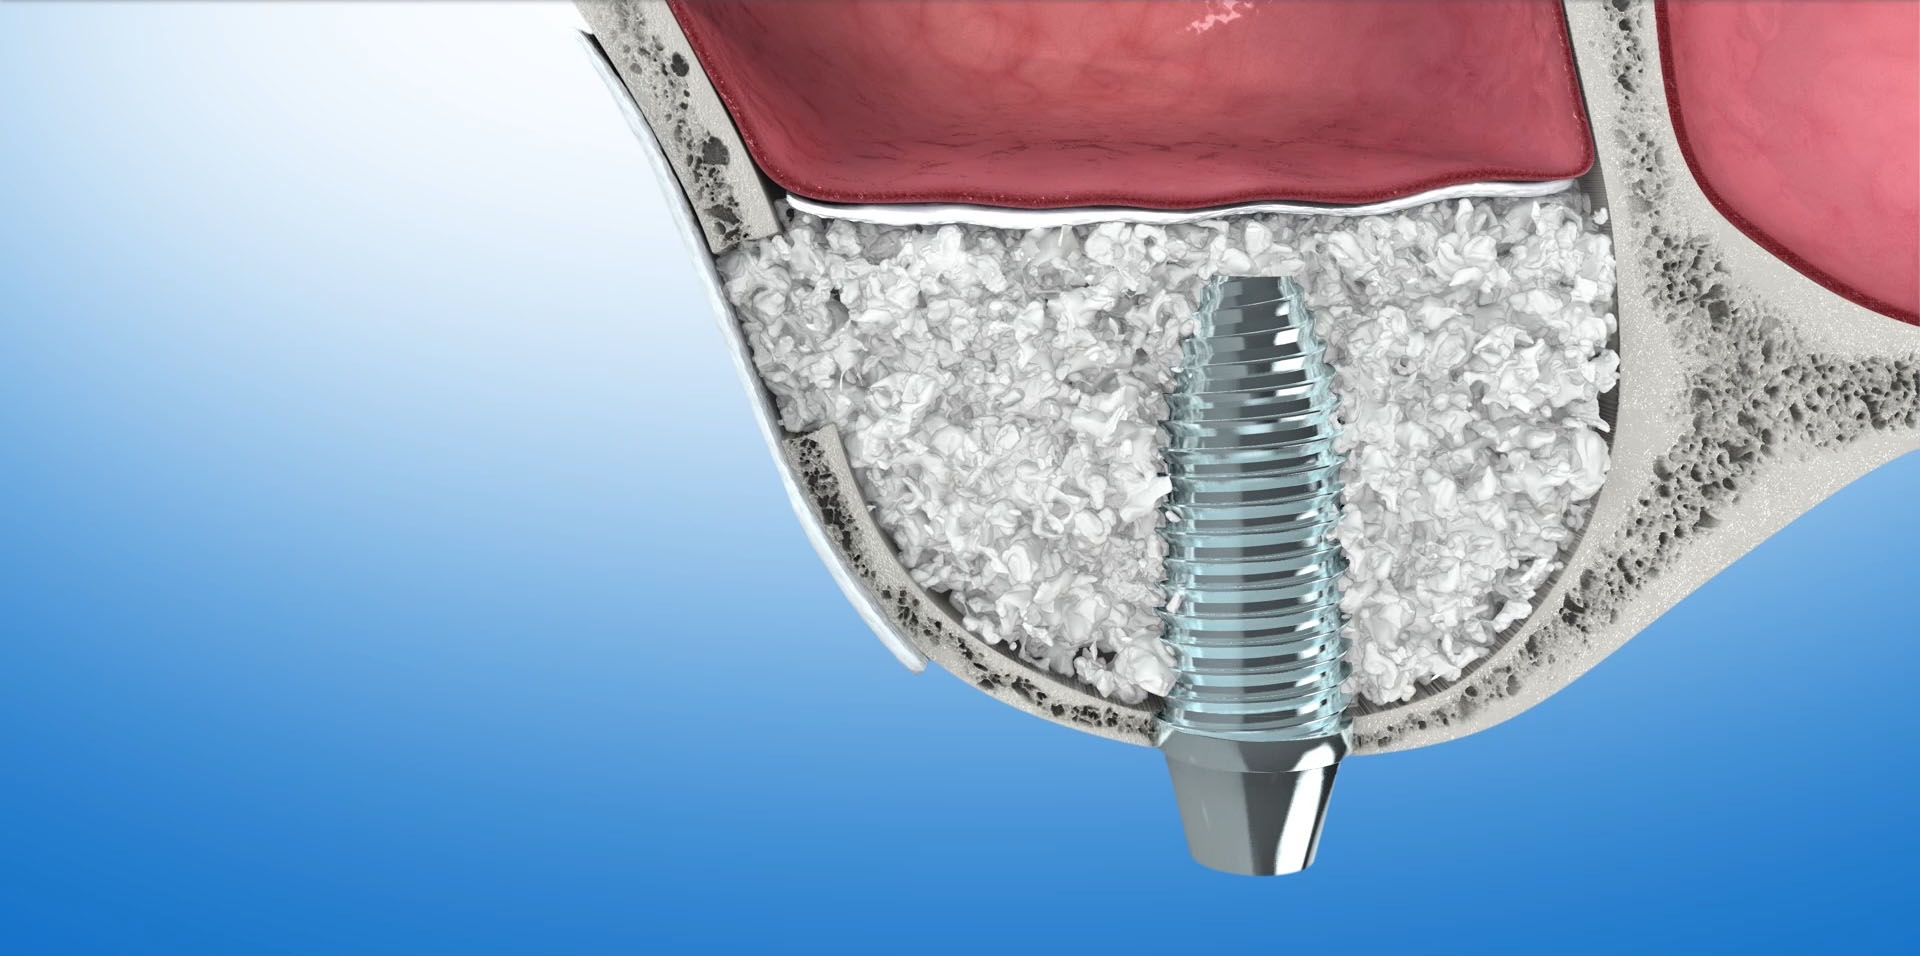

STEROWANA REGENERACJA KOŚCI (GBR-guided bone regeneration)

To odbudowa kości pacjenta do poziomu umożliwiającego implantację. Zanik kości wyrostka w wymiarze pionowym i poziomym powoduje powoduje w efekcie to, że jest on za niski lub zbyt wąski aby można było umieścić w nim implant dentystyczny. Ok. 40% przypadków wszystkich zabiegów implantacyjnych wymaga regeneracji kości. W jej wyniku odbudowana kość będzie stanowiła odpowiednie oparcie dla implantu oraz znacząco poprawi wynik estetyczny leczenia.

Do sterowanej regeneracji kości wykorzystywane są biomateriały – czyli substytuty kości oraz kość własną pacjenta. Często używane są równocześnie. Do pokrycia augumentatu czyli materiału odbudowującego kość używamy specjalnych membran, które stanowią barierę dla tkanek miękkich. Ogromna różnorodność na rynku biomateriałów pozwala na optymalny wybór w każdym konkretnym przypadku. W naszej Praktyce, zdecydowana większość zabiegów odbudowy kości przeprowadzana jest z zastosowaniem materiału kościozastępczego Bio-Oss oraz kolagenowych resorbowalnych membran Bio-Gide firmy Geistlich.

Bio-Oss

To materiał kościozastępczy produkowany z kości wołowych. W trakcie procesu produkcyjnego usuwane są z niego wszystkie składniki mogące powodować przenoszenie chorób lub wywoływać reakcje alergiczne. Naturalna struktura mineralna zostaje jednak nienaruszona. Wykazuje ona ogromne podobieństwo do struktury kości ludzkiej. Ten porowaty materiał o utkaniu ludzkiej kości stanowi doskonałe rusztowanie dla naczyń krwionośnych i komórek kościotwórczych. Stanowi matrycę, sieć dla tworzącej się tkanki kostnej. Z upływem czasu, ok.1mm w ciągu miesiąca, Bio-Oss ulega resorbcji, a miejsce po nim zajmuje nowo wytworzona kość.

Bio-Gide

To membrana zbudowana z oczyszczonych włókien kolagenowych. Stanowi ona barierę nie pozwalającą na kontakt tkanek miękkich z materiałem kościozastępczym. Prócz tego wspomaga proces gojenia się tkanki kostnej i tkanek miękkich.